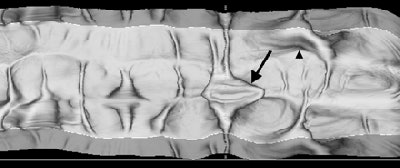

| Virtual Dissection (version 3.0, GE Healthcare) images of an 82-year-old man with ascending colon carcinoma seen at VC. Above, 360° virtual dissection image of right colon reveals lesion (arrow) that was considered to be a normal ileocecal valve. A 2.5-cm adenoma was found at colonoscopy. Normal valve can be identified in more proximal colon (arrowhead). Below, 3D endoluminal view shows colonoscopy-proven adenoma. Republished with permission of the American Journal of Roentgenology, from "CT colonography using 360-degree virtual dissection: A feasibility study," Johnson KT, Johnson CD, Fletcher JG, MacCarty RL, Summers RL, 2006 Jan;186(1):90-95. |